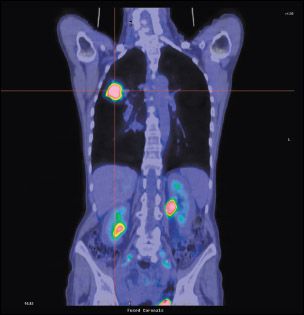

A PET/CT fusion image, frontal (coronal) section, showing non-small-cell lung cancer (NSCLC) of the right lung (on the left in this image). The large spot represents cancer of the lung at an advanced stage.